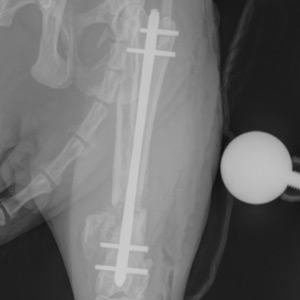

In May, Dr. Gleason performed the surgery using MSPCA-Angell West's new Ziehm Solo FD C-arm, an advanced imaging system that provides real-time, intra-operative images and allows surgeons to use minimally invasive approaches to fractures, leading to better outcomes and faster recovery. With this technology, she placed an interlocking nail to realign and stabilize Otis's femur. This repair method is both stronger than bone plates and better at preserving the bone's blood supply, which supports healing.

Amazingly, Otis was up and ready to use his leg the very next morning! Six weeks later, his follow-up X-rays showed a completely healed femur, and his foster family reported that he was back to doing what young cats do best — playing!

Top: Following his recovery, The Cat Connection found Otis a new home with a loving family of five and their dog, Poppy. Now he’s living his best life playing, cuddling, and finally safe, secure, and happy. Below: After discovering his limp, The Cat Connection brought Otis to the MSPCA-Angell West, where his femur underwent surgery to save his leg.